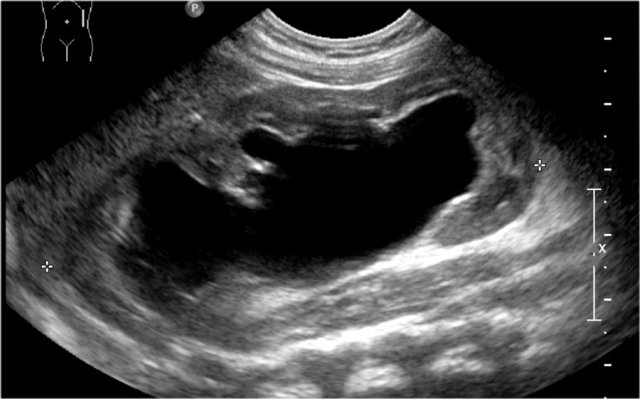

Here an ultrasound image of a five-month-old boy with an antenatally detected dilated pyelocalyceal system and no visible ureter, in accordance with a ureteropelvic junction stenosis.

On a sagittal image the dilated pyelocalyceal system is well seen.